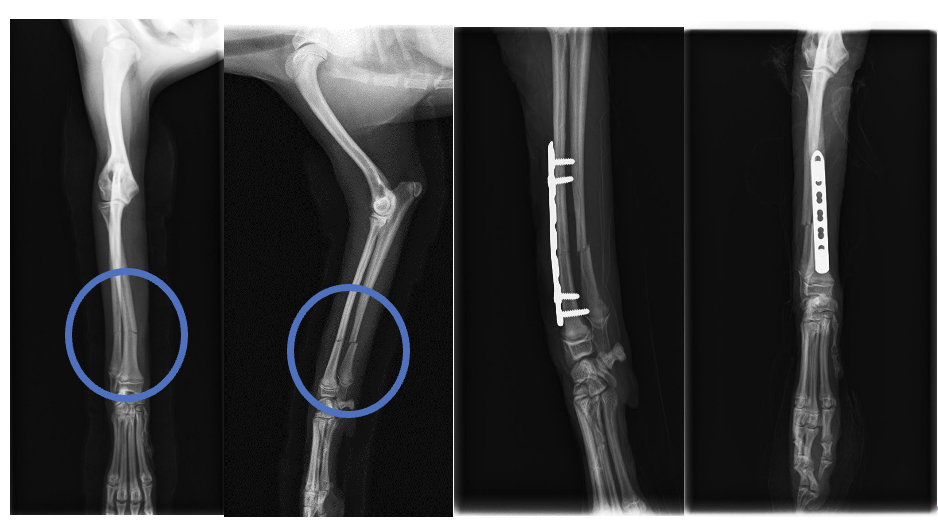

レントゲンを撮影すると橈骨と尺骨に骨折を認めました(青丸)ので、3日後にプレートを用いた整復手術を実施しました。